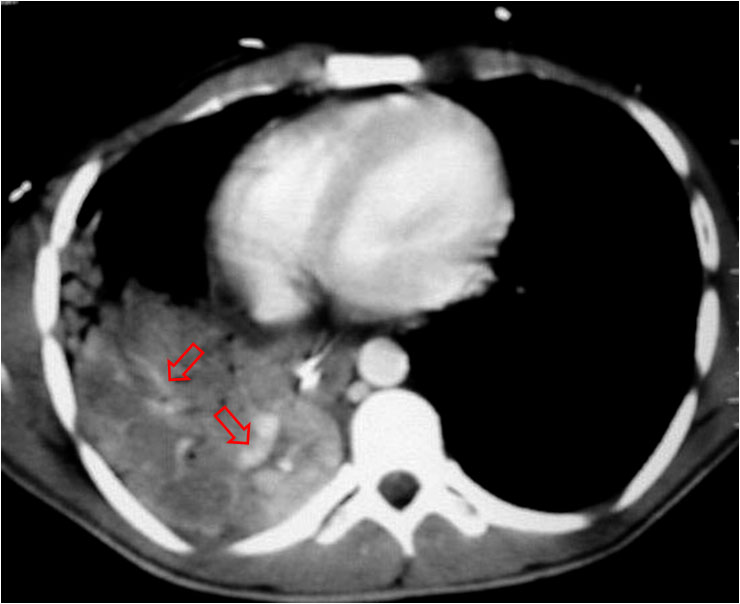

SIGNO DE LA JOROBA DE HAMPTON

Opacidad en cuña con base de contacto pleural, generalmente sin broncograma aéreo, que corresponde a infarto pulmonar. Aunque con frecuencia se localiza en el seno costofrénico lateral, puede encontrarse en otras localizaciones. La fotografía muestra una radiografía PA de tórax donde se observa una joroba de Hampton en el campo medio pulmonar derecho (flecha).